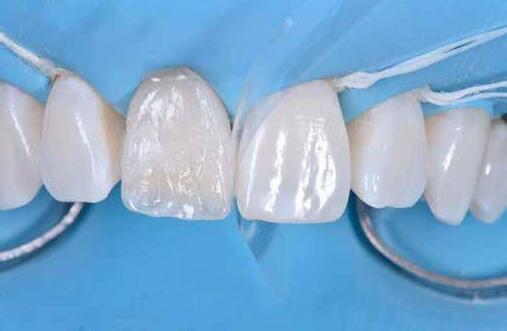

A cikkünkben bemutatásra kerülő eset ellátása során preparációt héjak készre vitele során a platinafólia technikát alkalmaztuk.

kívül vékonyak, és ezáltal a végleges rögzítésük előtt jelentős olyan minimál invazív kezelési eljárásnak számítanak, amely

elérni. A fent leírtak alapján bátran

preparációt nem igénylő héjak készítése mellett döntöttünk. A alkalmaztuk. Annak ellenére, hogy az elkészítésre kerülő héjak rendjelentős törésveszéllyel állunk szemben, összességében mégis amely segítségével kifogástalan esztétikai eredményeket lehet javasoljuk e módszer alkalmazását.

A fogászati kezelések során manapság már nem kizárólag az esztétikai megjelenés helyreállítására törekszünk. Sokszor a kedvezőtlen esztétikai megjelenés hátterében álló okok következményes módon a fogazat funkcionális működését is károsítják, így a kezelések során ezeknek a helyreállításával is foglalkoznunk kell. A különböző funkcionális és esztétikai diszkrepanciák kezelésére számtalan módszer létezik, ám ezen fogászati beavatkozások mindegyikében közös, hogy a kivitelezésük során nagyon szoros együttműködésre van szükség a kezelést végző fogorvos és a munkáját segítő fogtechnikus között. Az alábbi esetbemutatás során egy fiatal hölgypáciens fogazatának héjak alkalmazásával történő esztétikai és funkcionális rehabilitációját szeretnénk ismertetni.

Esetbemutatás

A 19 éves hölgypáciens azzal a kéréssel jelentkezett a rendelőnkbe, hogy szebb fogakat szeretne. Az első konzultáció alkalmával megkérdeztük, hogy mi zavarja leginkább a fogazatának jelenlegi megjelenésében, valamint azt is megbeszéltük vele, hogy milyen végeredmény elérése esetén lenne maradéktalanul elégedett. Ebben az esetben a kezelési célokat az alábbiakban határoztuk meg:

A páciens fogazata esztétikai megjelenésének és funkcionális működésének a lehető legtöbb, saját foganyag megtartása mellett történő helyreállítása (1. és 3. ábra). A lehető legideálisabb esztétikai végeredmény elérése érdekében néhány esetben a fogak alakjának módosítá -

sára is szükség van (2. és 4. ábra).

A kezelés megtervezése során kifejezett jelentősége van annak, hogy jó kommunikáció legyen a páciens, a fogorvos és a fogtechnikus között. A páciens leendő fogazatának természetes megjelenését a kezelésben részt vevő team szakmai felkészültsége, gyakorlati tapasztalata és a kezelés sikerességének irányába történő elkötelezettsége biztosítja. A beavatkozások megkezdése előtt megtörtént a páciens anamnézisének a felvétele, valamint a klinikai kivizsgálását is elvégeztük. Ezt követően lenyomatokat készítettünk a kiindulási állapotról, majd a kiindulási helyzetet extra- és intraorális fotók segítségével is rögzítettük (13. a-c. ábra).